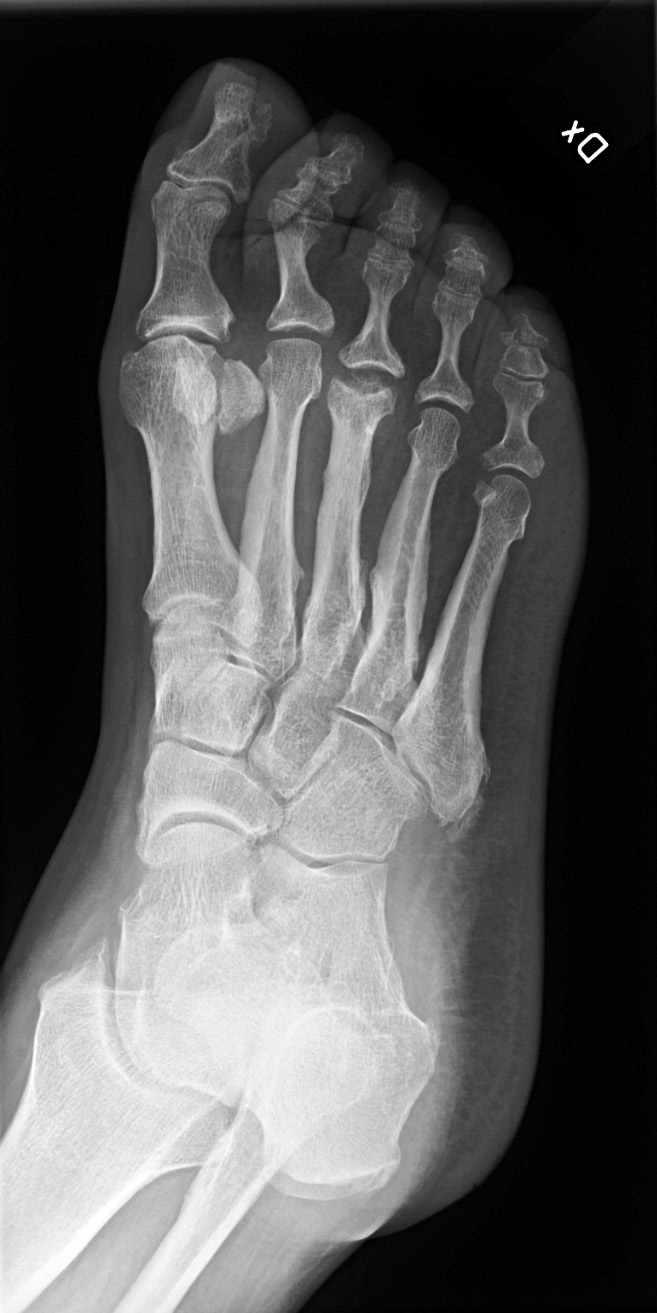

Slätröntgen utförd i den tidiga fasen av akut Charcotfot visar inga skelettförändringar (grad 0) men bör alltid genomföras för att utesluta fraktur och kartlägga om Charcotfot med skelettförändringar har hunnit uppstå (grad 1). Det kan däremot inte nog betonas att normalt fynd vid slätröntgen av foten inte på något sätt utesluter akut Charcotfot [27].

Slätröntgenbild som visar frakturering av talus och os naviculare i anslutning till Choparts led.